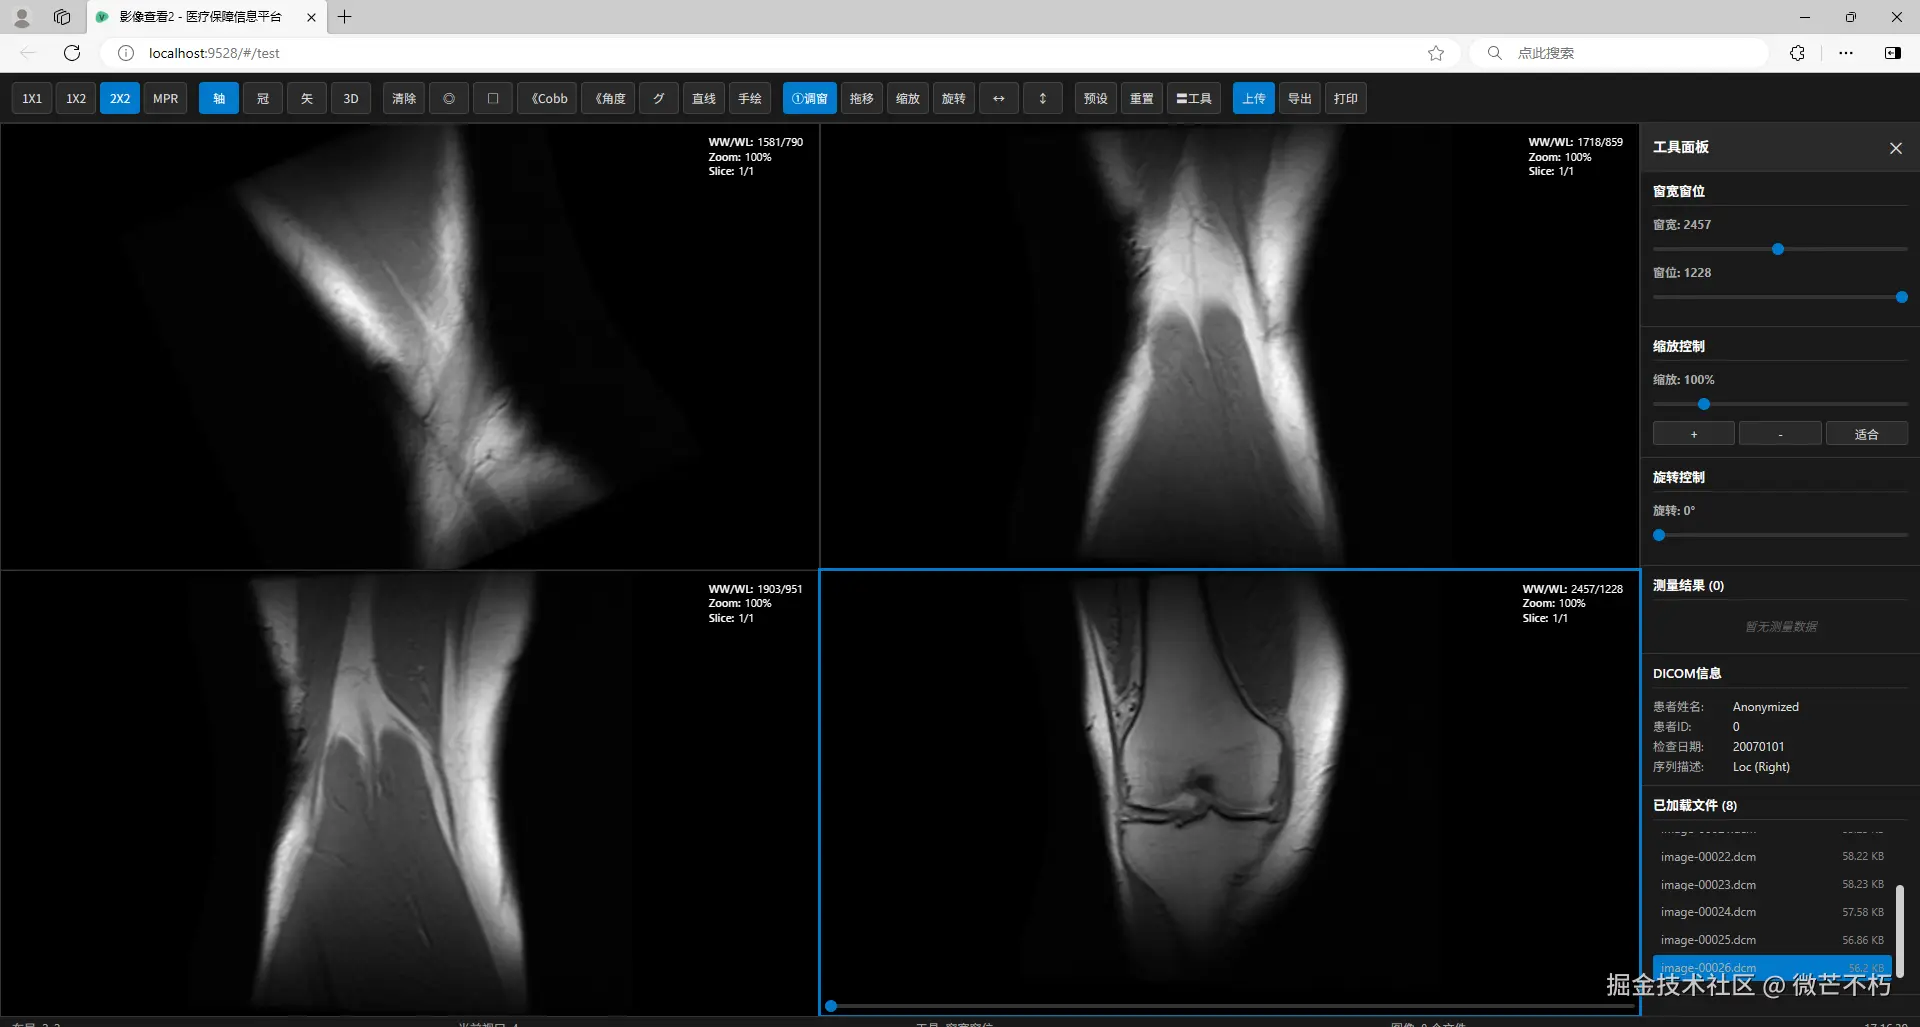

前端竟能做出这种专业医疗工具?DICOM Viewer 医学影像查看器

🏥【DICOM Viewer】

🖼️ 二、主显示区域 —— 多视口渲染引擎

📐 1. 布局容器(viewport-layout)

根据 layout 动态生成 1/2/4 个 .viewport-item

每个视口包含:

• div.dicom-element:Cornerstone 渲染画布

• div.placeholder:未加载时的占位提示

• div.viewport-overlay:叠加显示 WW/WL、Zoom、Slice 信息

• input.slice-slider:切片选择滑块(当前未启用多帧,固定为 1/1)